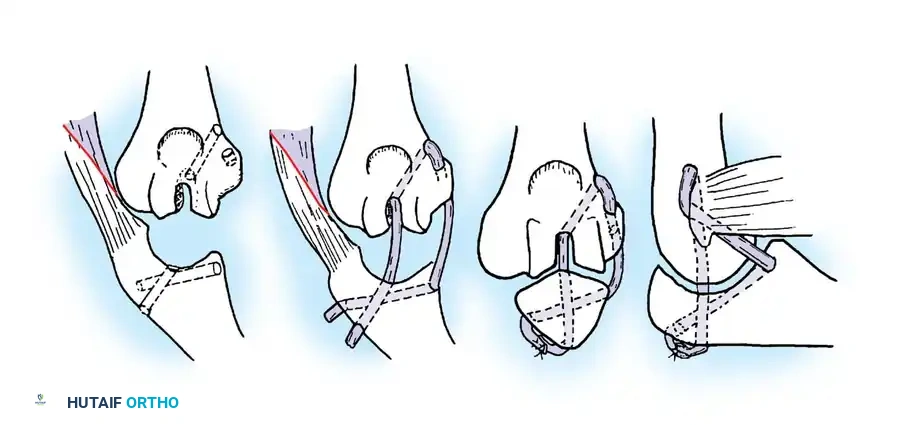

Fig. 58-26 Speed technique of open reduction. A, Incision and ulnar nerve isolation. B, Triceps aponeurosis reflected distally; subperiosteal stripping of muscles. C, Lateral view showing extent of mobilization. D, V-Y closure.

Subperiosteally free all muscle attachments from the distal humerus, both anteriorly and posteriorly.

Aggressive subperiosteal elevation is required to mobilize the distal humerus completely.

Release the attachments of the joint capsule and collateral ligaments around the humeral condyles. Mobilizing the tissues around the medial condyle and anterior humerus can be exceptionally difficult due to scarring, but complete mobilization of the distal humerus is non-negotiable for reduction.

Joint Debridement and Reduction

Extensive callus and heterotopic ossification are typically found on the posterior humerus and within the olecranon fossa.

Use a rongeur and high-speed burr to meticulously clear the olecranon and coronoid fossae of all fibrous tissue and callus.

Once the distal humerus is free, expose the radial head and clear the trochlear notch of the ulna. To reduce the joint, apply gentle traction, rotate the forearm, and press on the anterior surface of the capitellum to lever the radial head anteriorly into position. If resistance is met, do not use excessive force; instead, widen the soft-tissue release to prevent iatrogenic cartilage damage. Once the radial head is reduced, slip the coronoid process distally and anteriorly over the trochlea.

Intraarticular Cruciate Ligament Reconstruction

Arafiles described the creation of an intraarticular "cruciate" ligament using tendon grafts to stabilize the joint while allowing flexion-extension exercises as early as 6 days postoperatively.

Fig. 58-24 A and B, Slot in trochlea and drill holes showing the course of the tendon graft. C and D, Completed repair acting as an intraarticular cruciate ligament. (From Arafiles RP: Neglected posterior dislocation of the elbow, J Bone Joint Surg 69B:199, 1987.)